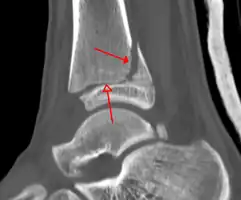

On X-rays, there can be a fracture of the medial malleolus, the lateral malleolus, or of the anterior/posterior margin of the distal tibia. [17] If both the lateral and medial malleoli are broken, this is called a bimalleolar fracture[18]. If the posterior malleolus is also fractured, this is called a trimalleolar fracture. [19]

A triplane fracture of the ankle as seen on CT